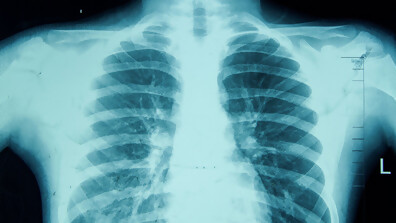

За образните методи в диагностиката и проследяването на заболяванията

130 години от откриването на рентгеновите лъчи